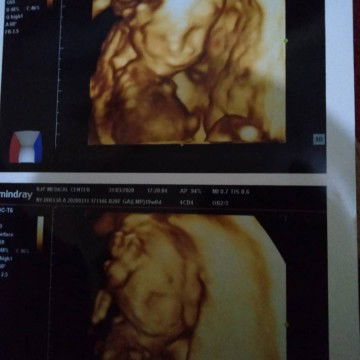

Hpl Agustus

Alhamdulilah udah ngeliat, secara ini baru pertama kali aku di USG. langsung nunjukin jk nya. dedek gak bisa diem banget yaaaa, terakhir ngasih pose salam lima jari sambil di taro di kepala, Masya Allah ?